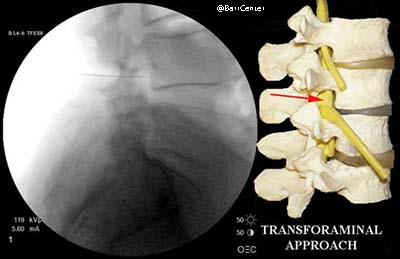

Transforaminal: the injection is placed in the foramina (opening) on the side of the spine near the exiting nerve. This is often the preferred method of injection as the needle and cortisone gets very close to the offending disc herniation yielding quick relief and often very good results.

For selective nerve root blocks and the transforaminal approach for an epidural steroid injection, the final needle position is just above the target nerve root.